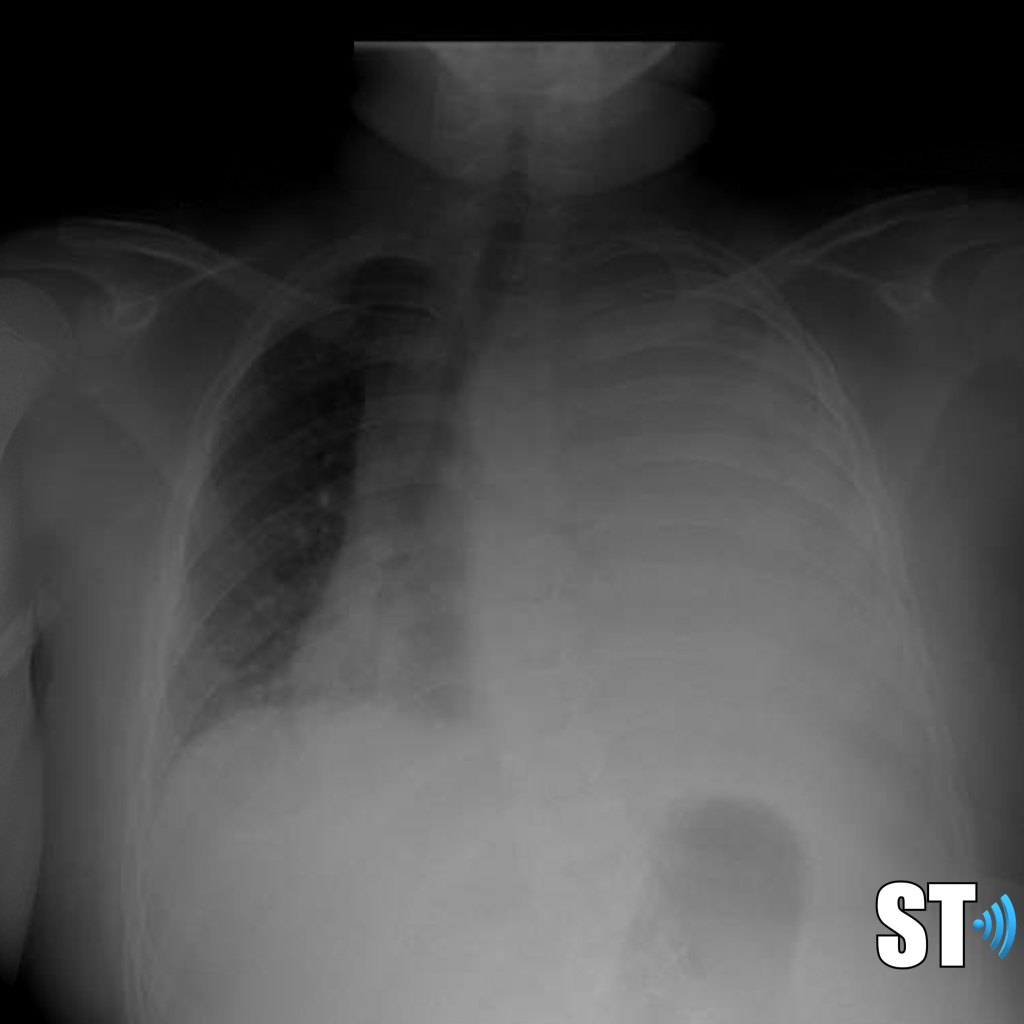

Imaging Findings

CT and Ultrasound findings of infected people are similar to other inflammatory, viral and bacterial respiratory syndromes. These are non-specific or pathognomic for Covid-19.

According to one study CT images showed pure ground-glass opacity (GGO) in 39 of 51 (77%) patients and GGO with reticular and/or interlobular septal thickening in 38 of 51 (75%) patients. GGO with consolidation was present in 30 of 51 (59%) patients, and pure consolidation was present in 28 of 51 (55%) patients. Forty-four of 51 (86%) patients had bilateral lung involvement.

Another study on ultrasound findings found these types of lesions:

- rough discontinuous pleural line

- subplueral consolidation

- visible b-lines

- pleural effusion

- poor blood flow on consolidated lung tissue with color doppler